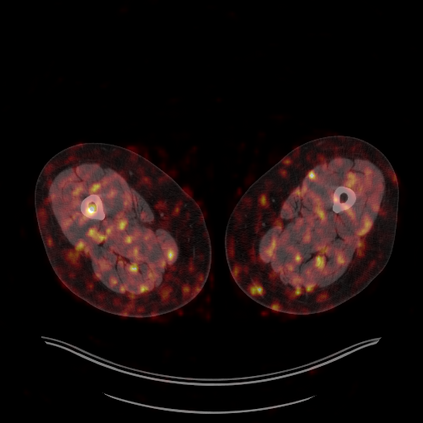

Medical images play a crucial role in assisting diagnosis, remote consultation, and academic research. However, during the transmission and sharing process, they face serious risks of copyright ownership and content tampering. Therefore, protecting medical images is of great importance. As an effective means of image copyright protection, zero-watermarking technology focuses on constructing watermarks without modifying the original carrier by extracting its stable features, which provides an ideal approach for protecting medical images. This paper aims to propose a fragile zero-watermarking model based on dual quaternion matrix decomposition, which utilizes the operational relationship between the standard part and the dual part of dual quaternions to correlate the original carrier image with the watermark image, and generates zero-watermarking information based on the characteristics of dual quaternion matrix decomposition, ultimately achieving copyright protection and content tampering detection for medical images.